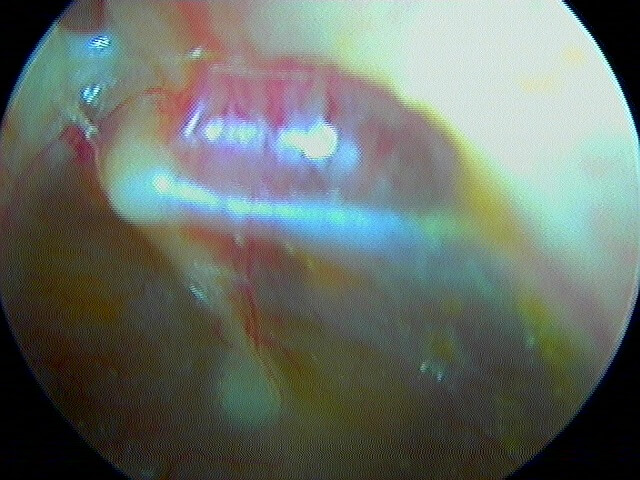

9 OTITE MOYENNE CHRONIQUE (OMC) NON CHOLESTÉATOMATEUSE

Perforation , otorrhée à répétition, otite muqueuse dans la caisse, lyse ossiculaire, rétraction tympanique. La limite entre l'otite atéléctasique perforée et l'otite moyenne chronique non cholestéatomateuse est souvent ésotérique...